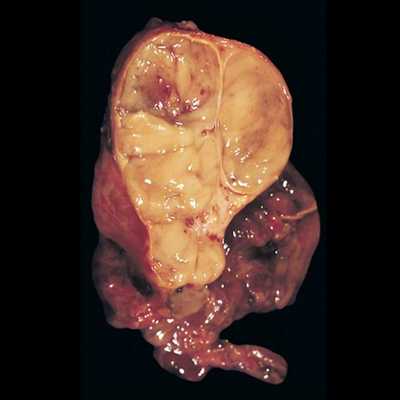

- Доброкачественная тимома (50-70% опухолей тимуса) макроскопически имеет вид одиночного инкапсулированного узла, диаметром не более 5 см. С учетом гистогенеза внутри этой группы выделяют медуллярную (тип А), смешанную (тип АВ) и преимущественно кортикальную (тип В1) тимому.

На рентгенограмме грудной клетки тимома имеет вид объемного образования неправильной формы, расположенного в переднем средостении. КТ грудной клетки значительно расширяет объем информации, полученный при первичной рентгендиагностике и в ряде случаев позволяет поставить морфологический диагноз. Уточнение локализации и взаимоотношения новообразования с соседними органами при КТ средостения позволяет в дальнейшем выполнить трансторакальную пункцию опухоли средостения, что чрезвычайно важно для гистологического подтверждения диагноза и верификации гистологического типа тимомы.